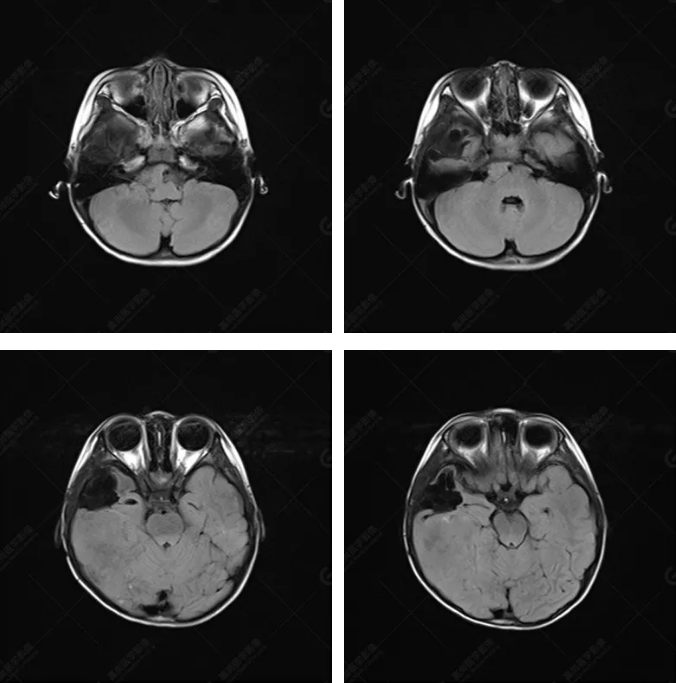

右側(cè)顳葉腫瘤切除術(shù)后(具體不詳):右側(cè)顳部骨質(zhì)不連續(xù)呈術(shù)后改變,右側(cè)顳葉術(shù)區(qū)見(jiàn)片狀長(zhǎng)T1長(zhǎng)T2信號(hào)影,F(xiàn)LAIR呈低信號(hào);術(shù)區(qū)后方右側(cè)顳枕葉見(jiàn)一巨大占位性病變影,邊界欠清,大小約6.2×5.8×4.3cm(前后×左右×上下),信號(hào)不均勻,T1WI呈等稍低信號(hào)間雜少許高信號(hào),T2WI呈高稍低混雜信號(hào),DWI示部分病灶彌散受限,相應(yīng)ADC圖減低,磁敏感序列見(jiàn)部分呈極低信號(hào),增強(qiáng)掃描可見(jiàn)明顯不均勻強(qiáng)化,鄰近硬腦膜及小腦幕增厚并明顯強(qiáng)化;另延髓右前方及右側(cè)橋小腦角區(qū)見(jiàn)一不規(guī)則形異常信號(hào)影,大小約3.2×1.3×3.7cm(左右×前后×上下),呈長(zhǎng)T1稍長(zhǎng)T2信號(hào),F(xiàn)LAIR呈等信號(hào),DWI未見(jiàn)受限,增強(qiáng)后明顯均勻強(qiáng)化,鄰近腦膜明顯強(qiáng)化。鄰近腦實(shí)質(zhì)及右側(cè)顳角明顯受壓;左側(cè)大腦半球未見(jiàn)局灶性信號(hào)異常,中線結(jié)構(gòu)稍左移。

非典型畸胎樣/橫紋肌樣瘤(AT/RT) 是一種高度惡性中樞神經(jīng)系統(tǒng)腫瘤,臨床罕見(jiàn),臨床表現(xiàn)無(wú)特異性,好發(fā)于 5 歲以下兒童,尤以 3 歲以下多見(jiàn),在兒童原發(fā)性中樞神經(jīng)系統(tǒng)(CNS)腫瘤中占 1%~3%。該腫瘤體積一般較大,幕上大于幕下,有明顯的占位效應(yīng)。該腫瘤成分復(fù)雜,囊變、出血、壞死常見(jiàn)。因此 AT/RT信號(hào)混雜,囊性部分呈 T1WI低、T2WI高信號(hào),增強(qiáng)后不強(qiáng)化;若瘤體出血,囊內(nèi)可見(jiàn)T1WI稍高信號(hào)、T2WI低信號(hào),實(shí)性部分在 T1WI上呈混雜等、低信號(hào),在T2WI 及 T2-FLAIR上呈混雜等高信號(hào),增強(qiáng)掃描后大部分呈環(huán)形條帶樣明顯強(qiáng)化,中心壞死區(qū)不強(qiáng)化。另外,該腫瘤實(shí)性成分在DWI上呈高信號(hào),說(shuō)明腫瘤細(xì)胞核密集,水分子擴(kuò)散明顯受限,提示該腫瘤惡性程度高,容易復(fù)發(fā)及轉(zhuǎn)移。